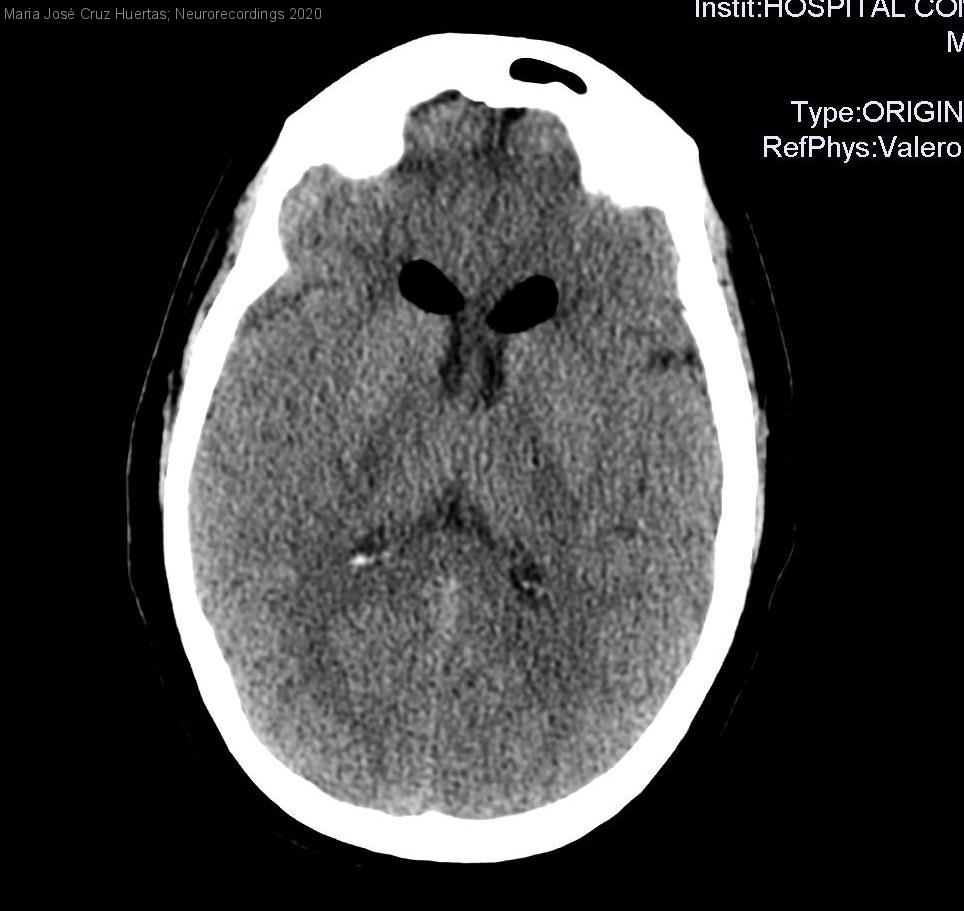

Diagnóstico final: NEUMOENCÉFALO SECUNDARIO A ANESTESIA INTRARRAQUÍDEA

Mujer de 69 años, diabetica y dislipémica. Física y cognitivamente independiente.

La paciente es sometida a histerectomía via vaginal como tratamiento de prolapso uterino y cistocele, para lo cual se decide aplicación de anestesia loco-regional intratecal....